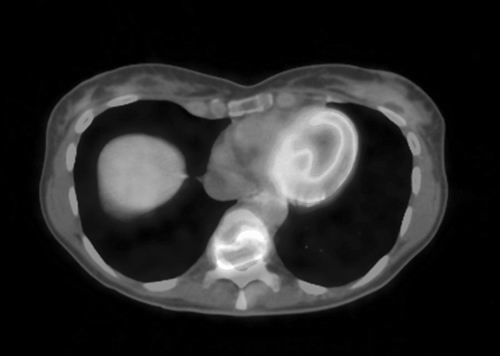

这种现象被称为“瓦氏效应”,研究者很快据此开发出通过追踪被癌细胞占据的放射性标记物葡萄糖分子对肿瘤成像的技术。芝加哥市伊利诺伊大学癌症生物学家Nissim Hay认为“瓦氏效应”的发现为新疗法的问世打开了一扇大门。Hay说:“既然我们能够有选择性地探测癌细胞,为何不能选择性地‘瞄准’它们?”